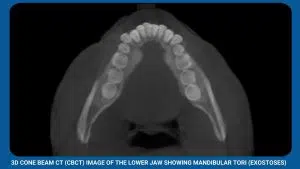

- Removal of excess bone (exostoses)- large and irregular chunks of excess bone may need to be removed to allow denture to fit properly.